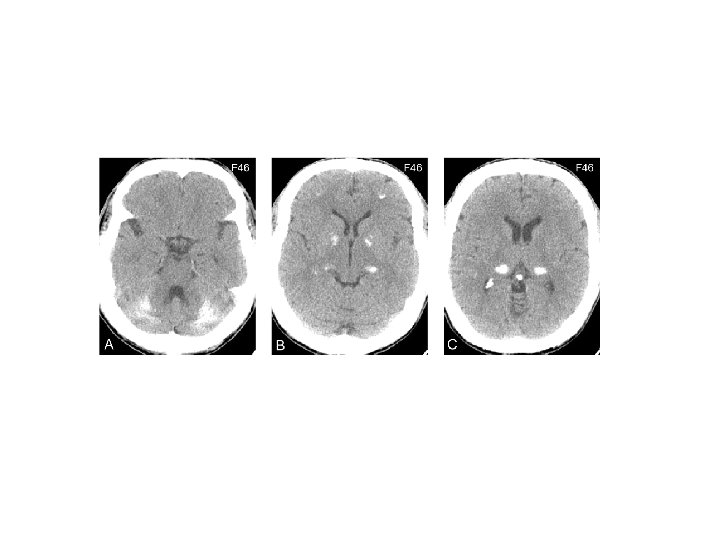

Atrofia cerebelar